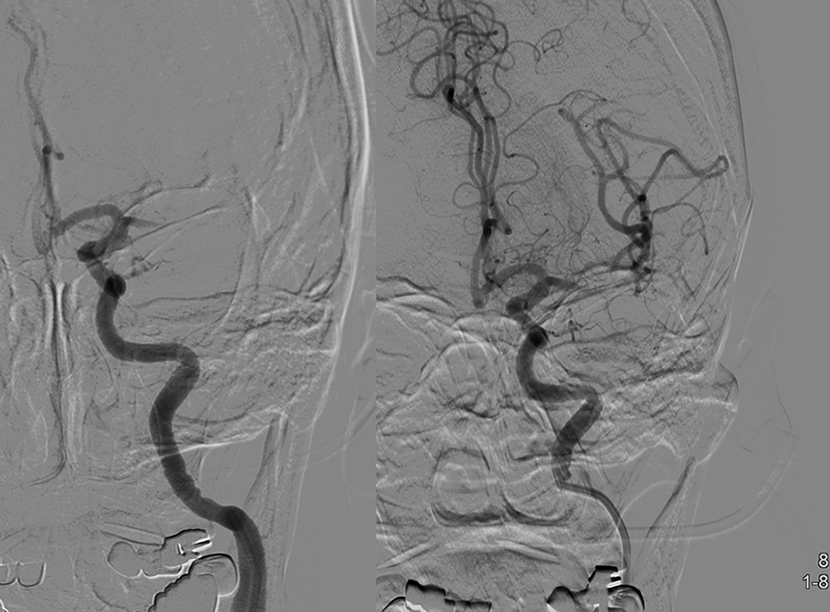

뇌MRA 와 뇌혈관조영술에서 좌측내경동맥의 심한 협착이 보임

성형술과 스텐트 삽입술을 시행하여, 우측의 수술전 사진과 비교시, 혈관을 넓혀주어 추가적인 뇌경색을 예방